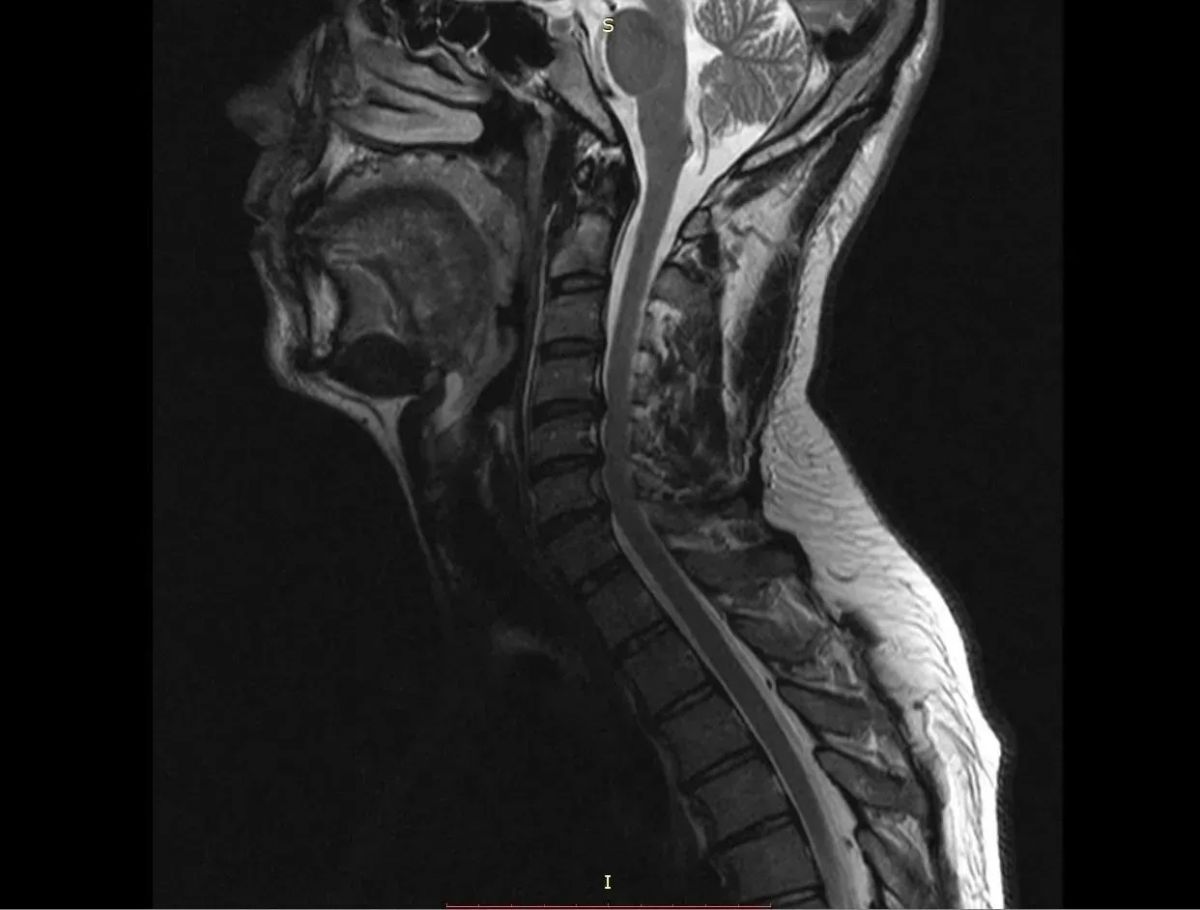

Нейрохирурги Воронежской городской клинической больницы скорой медицинской помощи №1 (БСМП №1) провели уникальную операцию 38-летнему пациенту, полностью восстановив ему свободу движений в руках. Команда под руководством заведующего отделением Павла Юрова устранила стеноз позвоночного канала, стабилизировала и укрепила шейный отдел титановыми конструкциями. Об этом сообщили в пресс-службе министерства здравоохранения Воронежской области 30 марта.

Мужчина годами мучился от остеохондроза шейного отдела. С августа 2025-го боль усилилась, распространилась на правую руку, добавив слабость и онемение. В стационаре мужчине поставили диагноз – диско-остеофитный стеноз позвоночного канала.